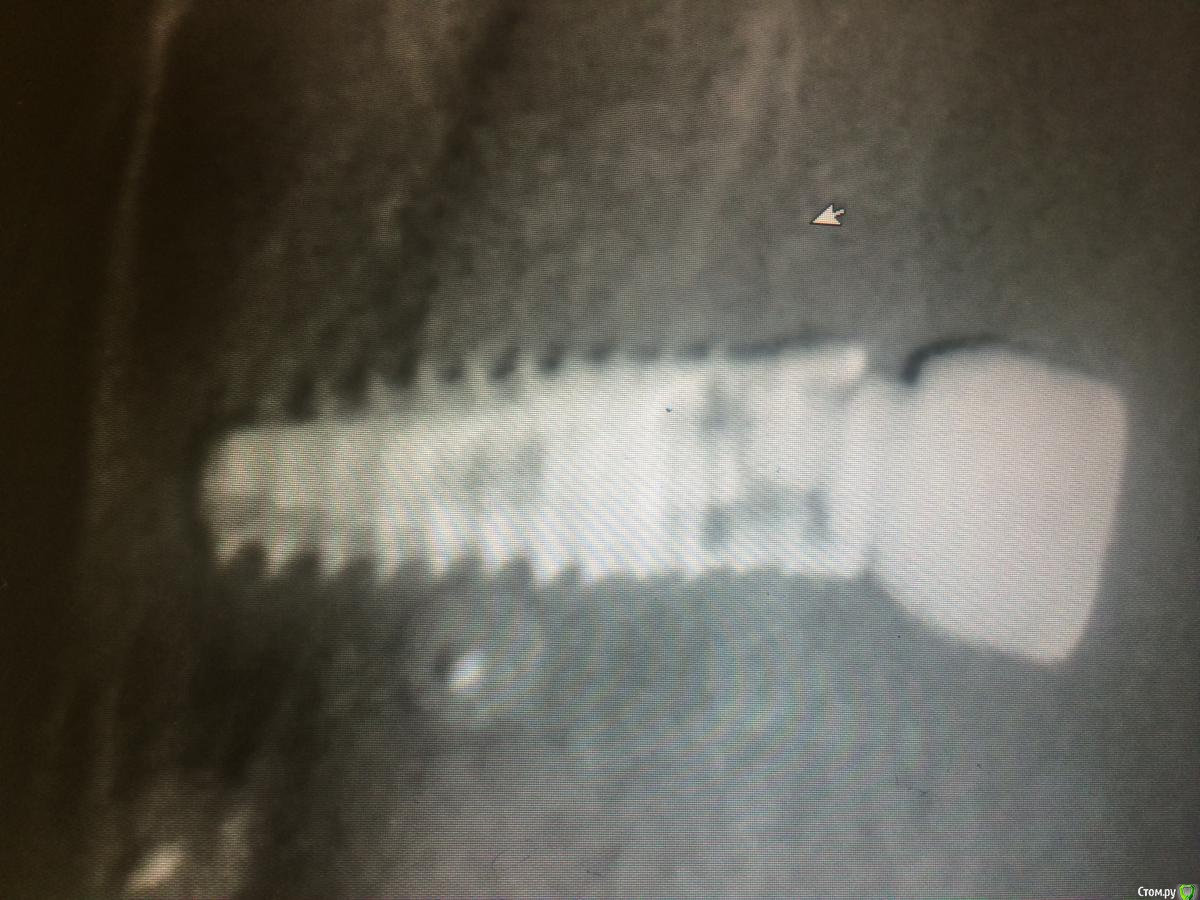

Mbegiev Опубликовано 31 марта, 2015 Поделиться Опубликовано 31 марта, 2015 У/з пробовал , что еще можно ? Не удаляя имплантат))Система xive Ссылка на комментарий

Mbegiev Опубликовано 31 марта, 2015 Автор Поделиться Опубликовано 31 марта, 2015 От ортопеда вернулся таким) говорит не шел по резьбе решил под нагрузкой.. Ссылка на комментарий

Mbegiev Опубликовано 16 апреля, 2015 Автор Поделиться Опубликовано 16 апреля, 2015 Закончилось все хорошо! Мы его победили) Набор для извлечения и нарезки новой резьбы нам помог. 2 Ссылка на комментарий